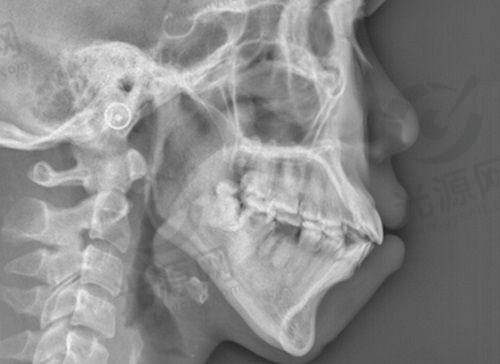

免疫系统由众多细胞和器官组成,负责识别和消灭外来入侵的物质。膨体(聚四氟乙烯)作为一种生物相容性材料,被广泛应用于整形外科中。尽管其相容性较好,但并非所有患者的免疫系统都能接受这种材料,因此会出现排异现象。